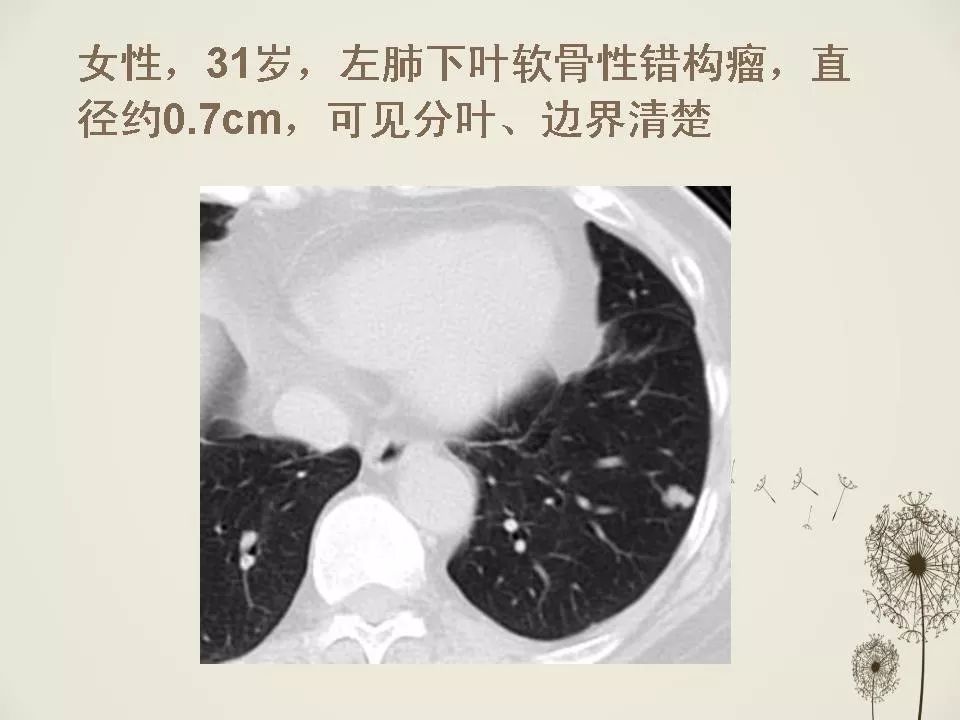

少见良性肺结节ct表现 | 影像天地